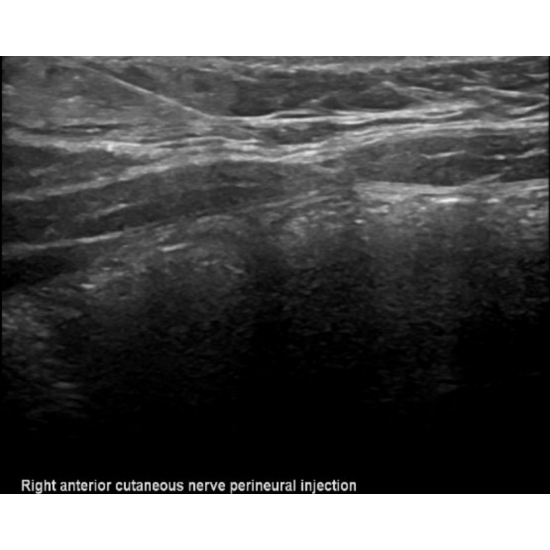

Patient returned for a diagnostic and therapeutic ultrasound guided anterior cutaneous nerve perineural corticosteroid injection. Two days post-injection, she returned to clinic with concern for post-injection steroid reaction and completed a course of oral steroids with resolution of reaction and significant improvement of symptoms. The patient had recurrence of symptom after one month and was referred to pediatric neurosurgery for planned surgical release and neurectomy procedure with pediatric plastic surgery. Photos below demonstrate the pre and post perineural injection visualization, respectively.

Case Photo #3 , Case Photo #4